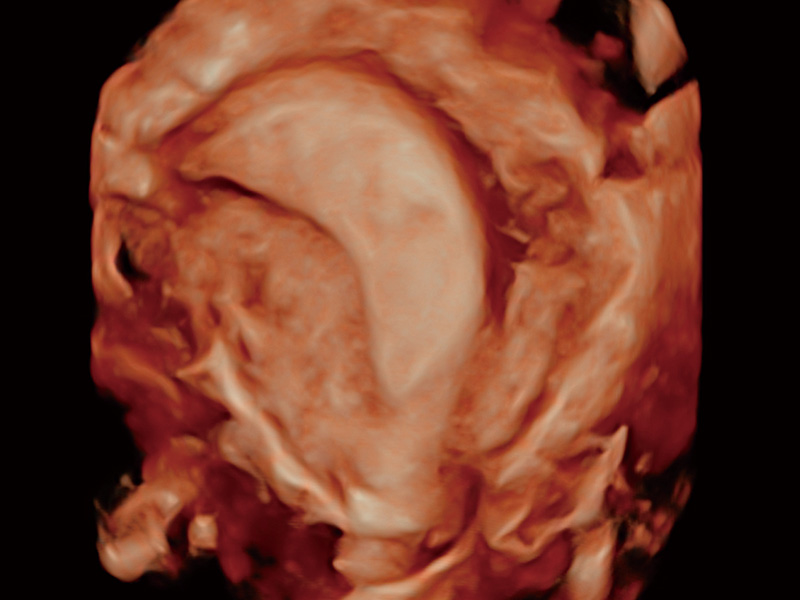

临床图

超声引导下胚胎移植